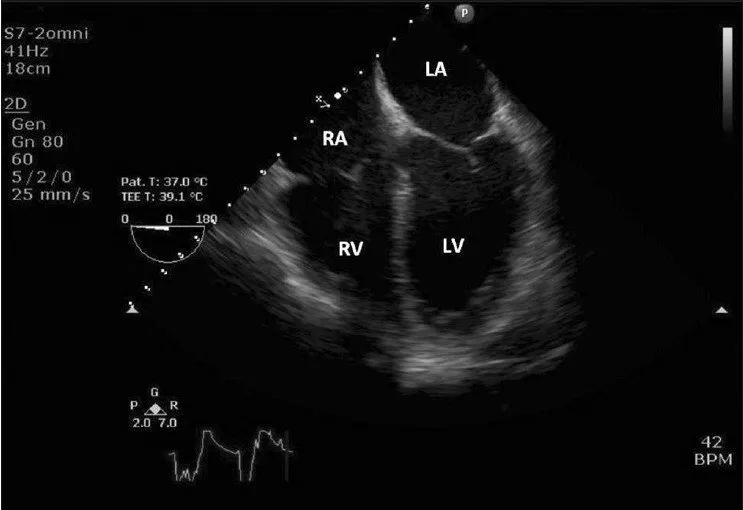

• Định nghĩa: Siêu âm tim qua thực quản (TEE) là một kỹ thuật chẩn đoán hình ảnh, trong đó một đầu dò siêu âm nhỏ được gắn vào một ống mềm, sau đó đưa qua đường miệng vào thực quản của bệnh nhân. Từ vị trí này, đầu dò sẽ phát ra sóng siêu âm để tạo ra hình ảnh chi tiết về tim và các cấu trúc lân cận.

• Ưu điểm: Do thực quản nằm rất gần tim, TEE cho phép thu được hình ảnh rõ nét và chi tiết hơn so với siêu âm tim qua thành ngực (TTE) thông thường. Điều này đặc biệt hữu ích trong việc đánh giá các cấu trúc nhỏ, nằm sâu hoặc bị che khuất bởi xương sườn và phổi.

• Kích thước và chức năng của các buồng tim (nhĩ và thất).

• Cấu trúc và chức năng của các van tim (van hai lá, van ba lá, van động mạch chủ, van động mạch phổi).

• Màng ngoài tim (lớp màng bao bọc bên ngoài tim).

• Các mạch máu lớn nối với tim (động mạch chủ, tĩnh mạch phổi).